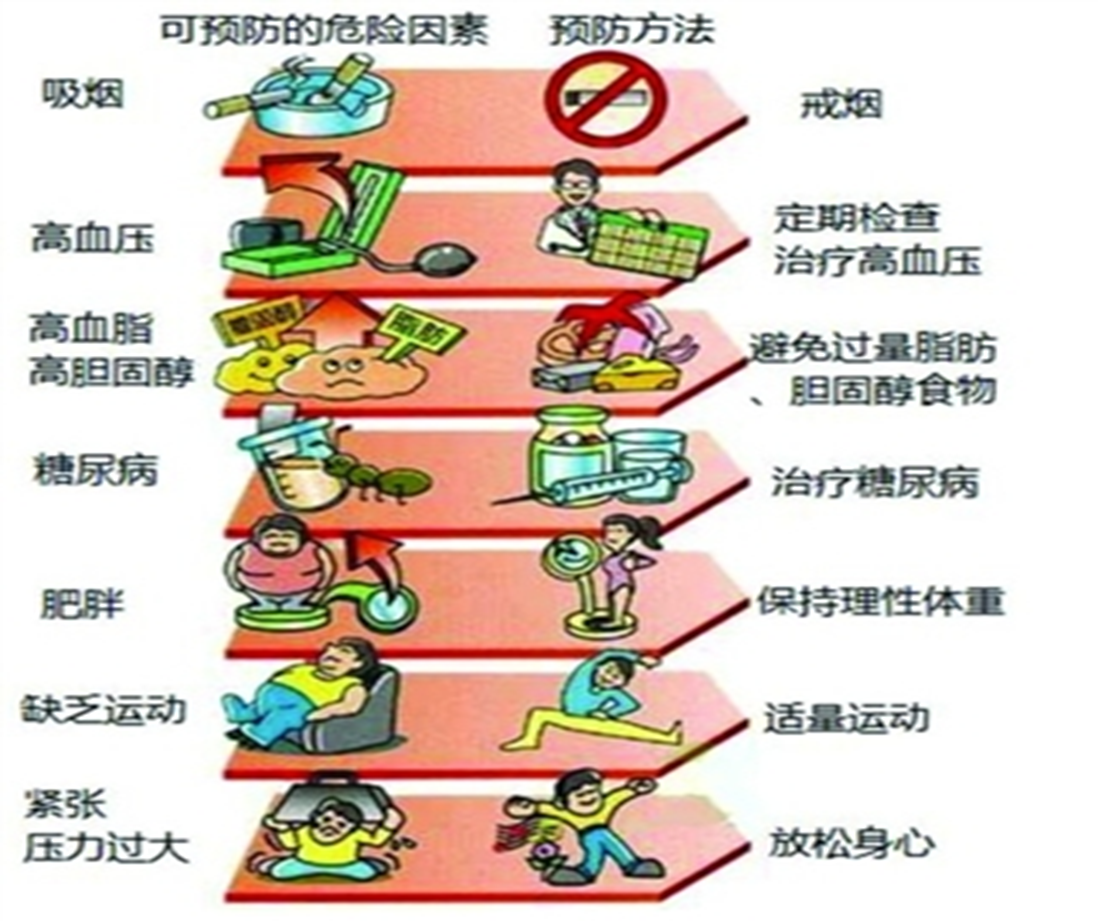

三、 脑卒中的危险

因素包括:高血压、高脂血症、糖尿病、冠心病、年龄、肥胖、酗酒、家族史等等,其中很大一部分是可以预防的危险因素,如下图,这也是可以干预的目标因素。